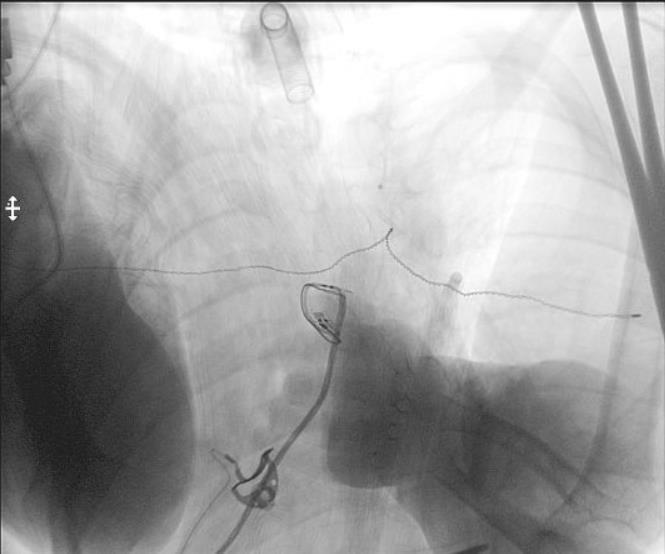

Adductor Longus L2, L3

Vastus Lateralis L3,L4

Tibialis Anterior L4, L5

Peroneus longus L5, S1

Gastrocnemius S1, S2

Abductor hallucis S1, S2

Sphincter S2